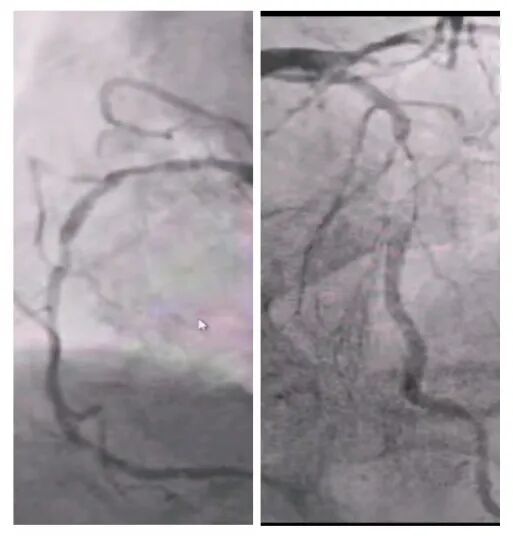

术前冠脉造影

手术当日8时30分,麻醉诱导平稳完成。在经食道超声实时监测下,体外循环管路顺利建立,心脏在低温停跳下显露术野。主刀医生采用“无接触技术”沿瘤体蒂部完整剥离肿瘤组织,避免碎片脱落;随后选取左侧乳内动脉吻合前降支,大隐静脉序贯吻合钝缘支与后降支,完成三支血管重建。125分钟的转机时间里,麻醉师全程维持平均动脉压在65-75mmHg,体外循环师精准调控流量至2.4L/min/m²。